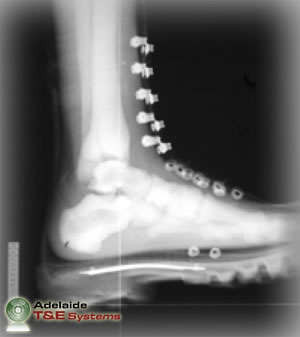

The principal method of injury assessment is standard medical examination, both physically and radiographically, to diagnose outcomes that often include dislocations, fractures and traumatic amputations.

The flash x-ray images above show the FSLLM’s response in millisecond intervals to 50g of plastic explosive buried 20mm below sand with 50mm of standoff. Note: images sourced from DSTO-TR-1829.